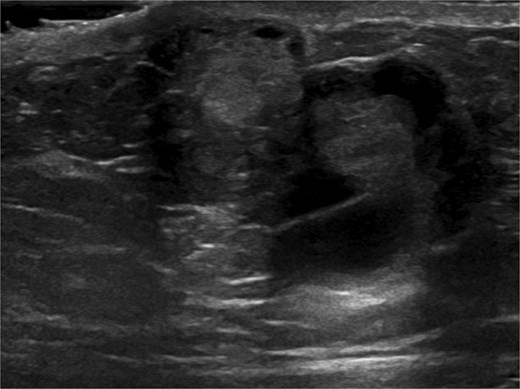

Ultrasound-guided core needle biopsy of the mass showed dissociated fragments of cribriform-like and papillary-like carcinoma (Figs 3 and 4).

Ultrasound of retroareolar area of palpable concern – first view.